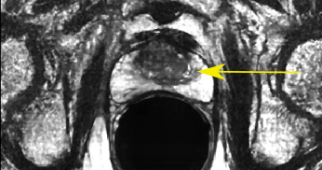

Fig. 4: SR result for anisotropic SRGAN using real data, yellow arrow indicates suspicious cancer region

Figure 4 is an example of axial and coronal views. The HR views portray the difference in resolution between the in-plane axial slice and the coronal and sagittal through-plane slices. The SR views show the anisotropic SRGAN outputs on the real HR data. The arrows in the top row of Figure 4 point to a suspicious region within the axial prostate. The LR axial image obtained by taking a through-plane slice from a coronal volume has lost all information about this region. The SR image is able to reconstruct the high frequency content and provides valuable edge and texture information. The anisotropic SRGAN method is able to improve the through-plane resolution by 8x while incurring only a slight resolution loss in the in-plane slice.